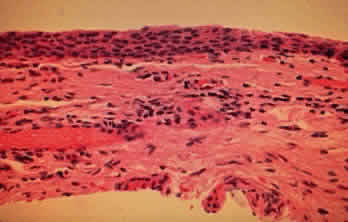

The conjunctival epithelium in CP shows squamous metaplasia, with parakeratosis and keratinization (Fig. 7).26 Mucus-producing goblet cells are scarce or lacking.11,27 Because the mitotic rate of conjunctival epithelium is higher in patients with CP, it has been suggested that CP is associated with hyperproliferation of the conjunctival epithelium, with a failure of conjunctival differentiation because of reduced goblet cells.28

In the early stages of conjunctival disease, granulation tissue is found beneath the conjunctival epithelium, with an infiltration predominantly of lymphocytes and plasma cells, with occasional eosinophils and relatively few neutrophils.13,26 Later, pronounced fibrosis takes place in the conjunctival stroma and is responsible for the conjunctival shrinkage that characterizes the disease.9,10 Hyperproliferation of conjunctival fibroblasts from patients with CP has been demonstrated in tissue culture.29 One study described perivascular inflammatory cell infiltration in 20% of specimens and substantial mast cell participation and degranulation.4 In addition to the chronic inflammatory cells typical of CP, conjunctival biopsy specimens from patients with acute manifestations of CP show numerous neutrophils within and beneath the conjunctival epithelium (Fig. 8).15